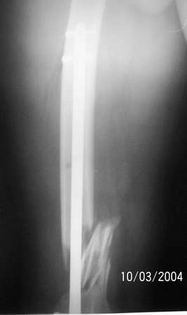

A 34 year old male was injured in a car accident.

The femur injury was treated by long retrograde interlocking nail.

It was used ORTHFIX Retrograde nailing System, diameter 11.